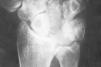

Figura 5. En la radiografía de perfil se aprecia la inestabilidad en DISI del implante.

Debido a esta falta del implante hemos observado en un 20% de los casos luxación y subluxación de la artroplastia, en un 30% inestabilidad en DISI y en un 10% en VISI. La incidencia de imágenes líticas intraóseas y sinovitis por liberación de partículas de silicona en nuestra serie es del 40%. Surgen por la abrasión y el desgaste del implante y producen una sinovitis hipertrófica con granulomas por silicona.19 Microscópicamente se aprecia la respuesta del huésped a estas partículas como una reacción de células gigantes a cuerpo extraño. Los leucocitos y macrófagos fagocitan el material, pero la silicona no se afecta por las enzimas lisosomales, lo que induce una sinovitis reactiva que no es exclusiva de la silicona (PMMA, polietileno y otros materiales metálicos), estando siempre en relación con el tamaño de la partícula. Las partículas de silicona son de 30 a 60 micras de diámetro. Estos implantes se han desaconsejado para la sustitución del escafoides y del semilunar, ya que al estar sometidos a importantes cargas de compresión se produce su fragmentación.31 Los factores que desgastan el implante de silicona y contribuyen a la formación de partículas son las fuerzas excesivas a través del implante debidas a la asociación de inestabilidad o de colapso, una malposición o exceso de tamaño, exceso de movilidad y abuso de la actividad diaria.43,44